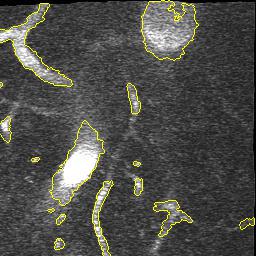

Refer to caption

(a) Original Image

(b) SNIC, DICE 81.6%

(c) EA, DICE 81.3%

(d) Ours, DICE 87.9%

(e) Ground Truth

Figure 7: Qualitative Comparison of Superpixel Algorithms on an image from DeepVess.

The results in Table 1 show that our approach performs best across other superpixel algorithms in an end-to-end segmentation pipeline. Based on this observation we conclude that the slight drop in compactness we observed in the natural image experiments with respect to EA does not affect the quality of post-processing. Moreover, the results stress our method’s robustness with respect to noise. It is also worth noting that it closely matches the performance of a trained neural networkand the second human annotation on this dataset. While the Double-DIP seems to work on natural images with a saliency estimate, it does not converge on noisy microscopic data which is why we decided to stop the optimization after 500 steps. In Figure 7 we can see superpixel based foreground predictions generated from a DeepVess slice. While SNIC fails to match superpixels to vessel structures and overfits to noise artifacts, EA and our method produce smoother superpixels. However, the Deep Decoder is better at detecting low-intensity shapes and adhering to vessel boundaries, as it can be seen around the ground truth objects in the top left part in Figure 7, which is why the segmentation pipeline works best with our method as a superpixel generator.